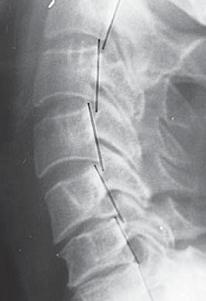

При таких патологических процессах фиброзное кольцо растрескивается более интенсивно именно в зонах «хрящевой метаплазии», что в дальнейшем приводит к развитию протрузий или грыж межпозвонковых дисков. Вторичность поражения фиброзного кольца подтверждается тем, что трещины распределяются на кольцо изнутри межпозвонкового диска и степень их распространения пропорциональна выраженности деструкции пульпозного ядра. При сегментарной нестабильности происходят движения в виде чрезмерного сгибания и разгибания, а также несвойственные скольжения позвонков кпереди или кзади. При функциональной рентгенографии это определяется как смещение тела вышележащего позвонка при сгибании несколько кпереди (рентгенограмма № 2), а при разгибании — кзади (рентгенограмма № 3), или изменение равномерной дуги (лордоза) с локальным выпрямлением (или усугублением).

Рентгенограмма № 3